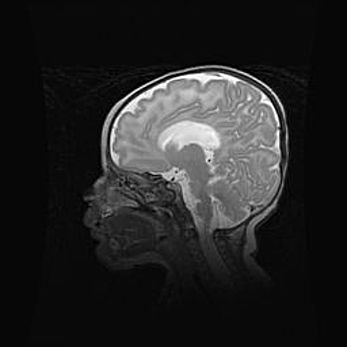

Аномалия Денди-Уокера. Признаки гипоплазии мозолистого тела.

Возраст: 5 месяцев 3 дня

Вес: 5550 г

Пол: мужской

Окружность головы: 39 см

Срок гестации: 40 недель

Аномалия Денди-Уокера – это порок развития головного мозга, для которого характерна триада симптомов: гипотрофия или аплазия червя мозжечка и/или полушарий мозжечка, расширение четвёртого желудочка с формированием ликворной кисты задней черепной ямки, гипертензионная гидроцефалия различной степени.

Гипоплазия мозолистого тела относится к дефектам внутриутробного этапа развития мозговой ткани, возникающим в процессе закладки структур головного мозга, что происходит на начальных этапах развития эмбриона.